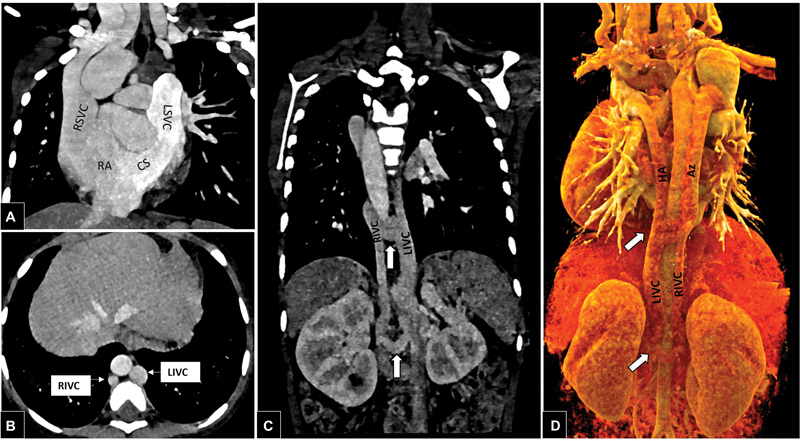

持续性左心静脉(LACV)是一种罕见的肺静脉异常,其特征是胚胎期肺脏与全身的通讯持续存在。它通常与左心梗阻性病变有关,如左心发育不全综合征和二尖瓣闭锁。上腔静脉(SVC)和下腔静脉(IVC)的完全重复是罕见的,这是由于基数静脉系统多步骤发育的畸变而发生的。文献中有双SVC和IVC共存的报道;然而,其发生与持续性左心房静脉至今未见报道。目前的病例描述了这些复杂的肺静脉和全身静脉异常的罕见共存:双SVC和IVC患儿的持续左房心静脉。胚胎发育和可能的畸变导致这些异常也详细。

Persistent levoatriocardinal vein (LACV) is a rare pulmonary venous anomaly characterized by persistence of embryonic pulmonary to systemic communication. It is commonly associated with obstructive lesions of the left heart, such as hypoplastic left heart syndrome and mitral atresia. Complete duplication of the superior vena cava (SVC) and inferior vena cava (IVC) is rare, and occurs due to aberrations in the multistep development of the cardinal venous system. Coexistence of double SVC and IVC has been reported in the literature; however, their occurrence with persistent levoatriocardinal vein is hitherto unreported. The current case describes a rare coexistence of these complex pulmonary and systemic venous anomalies: persistent levoatriocardinal vein in a child with double SVC and IVC. The embryological development and possible aberrations leading to these anomalies are also detailed.